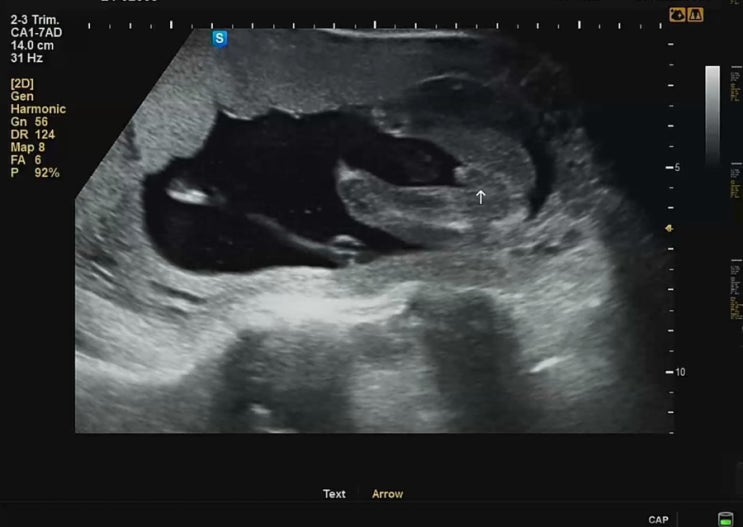

16주5일 2차기형아검사 결과 | 아기 성별확인 돌고래, 대봉감 꿈 태몽

안녕하세요. 데이지영 입니다:) 지난 임신 12주5일에 1차기형아검사를 받고 4주 뒤인 16주5일차에 2차기형...